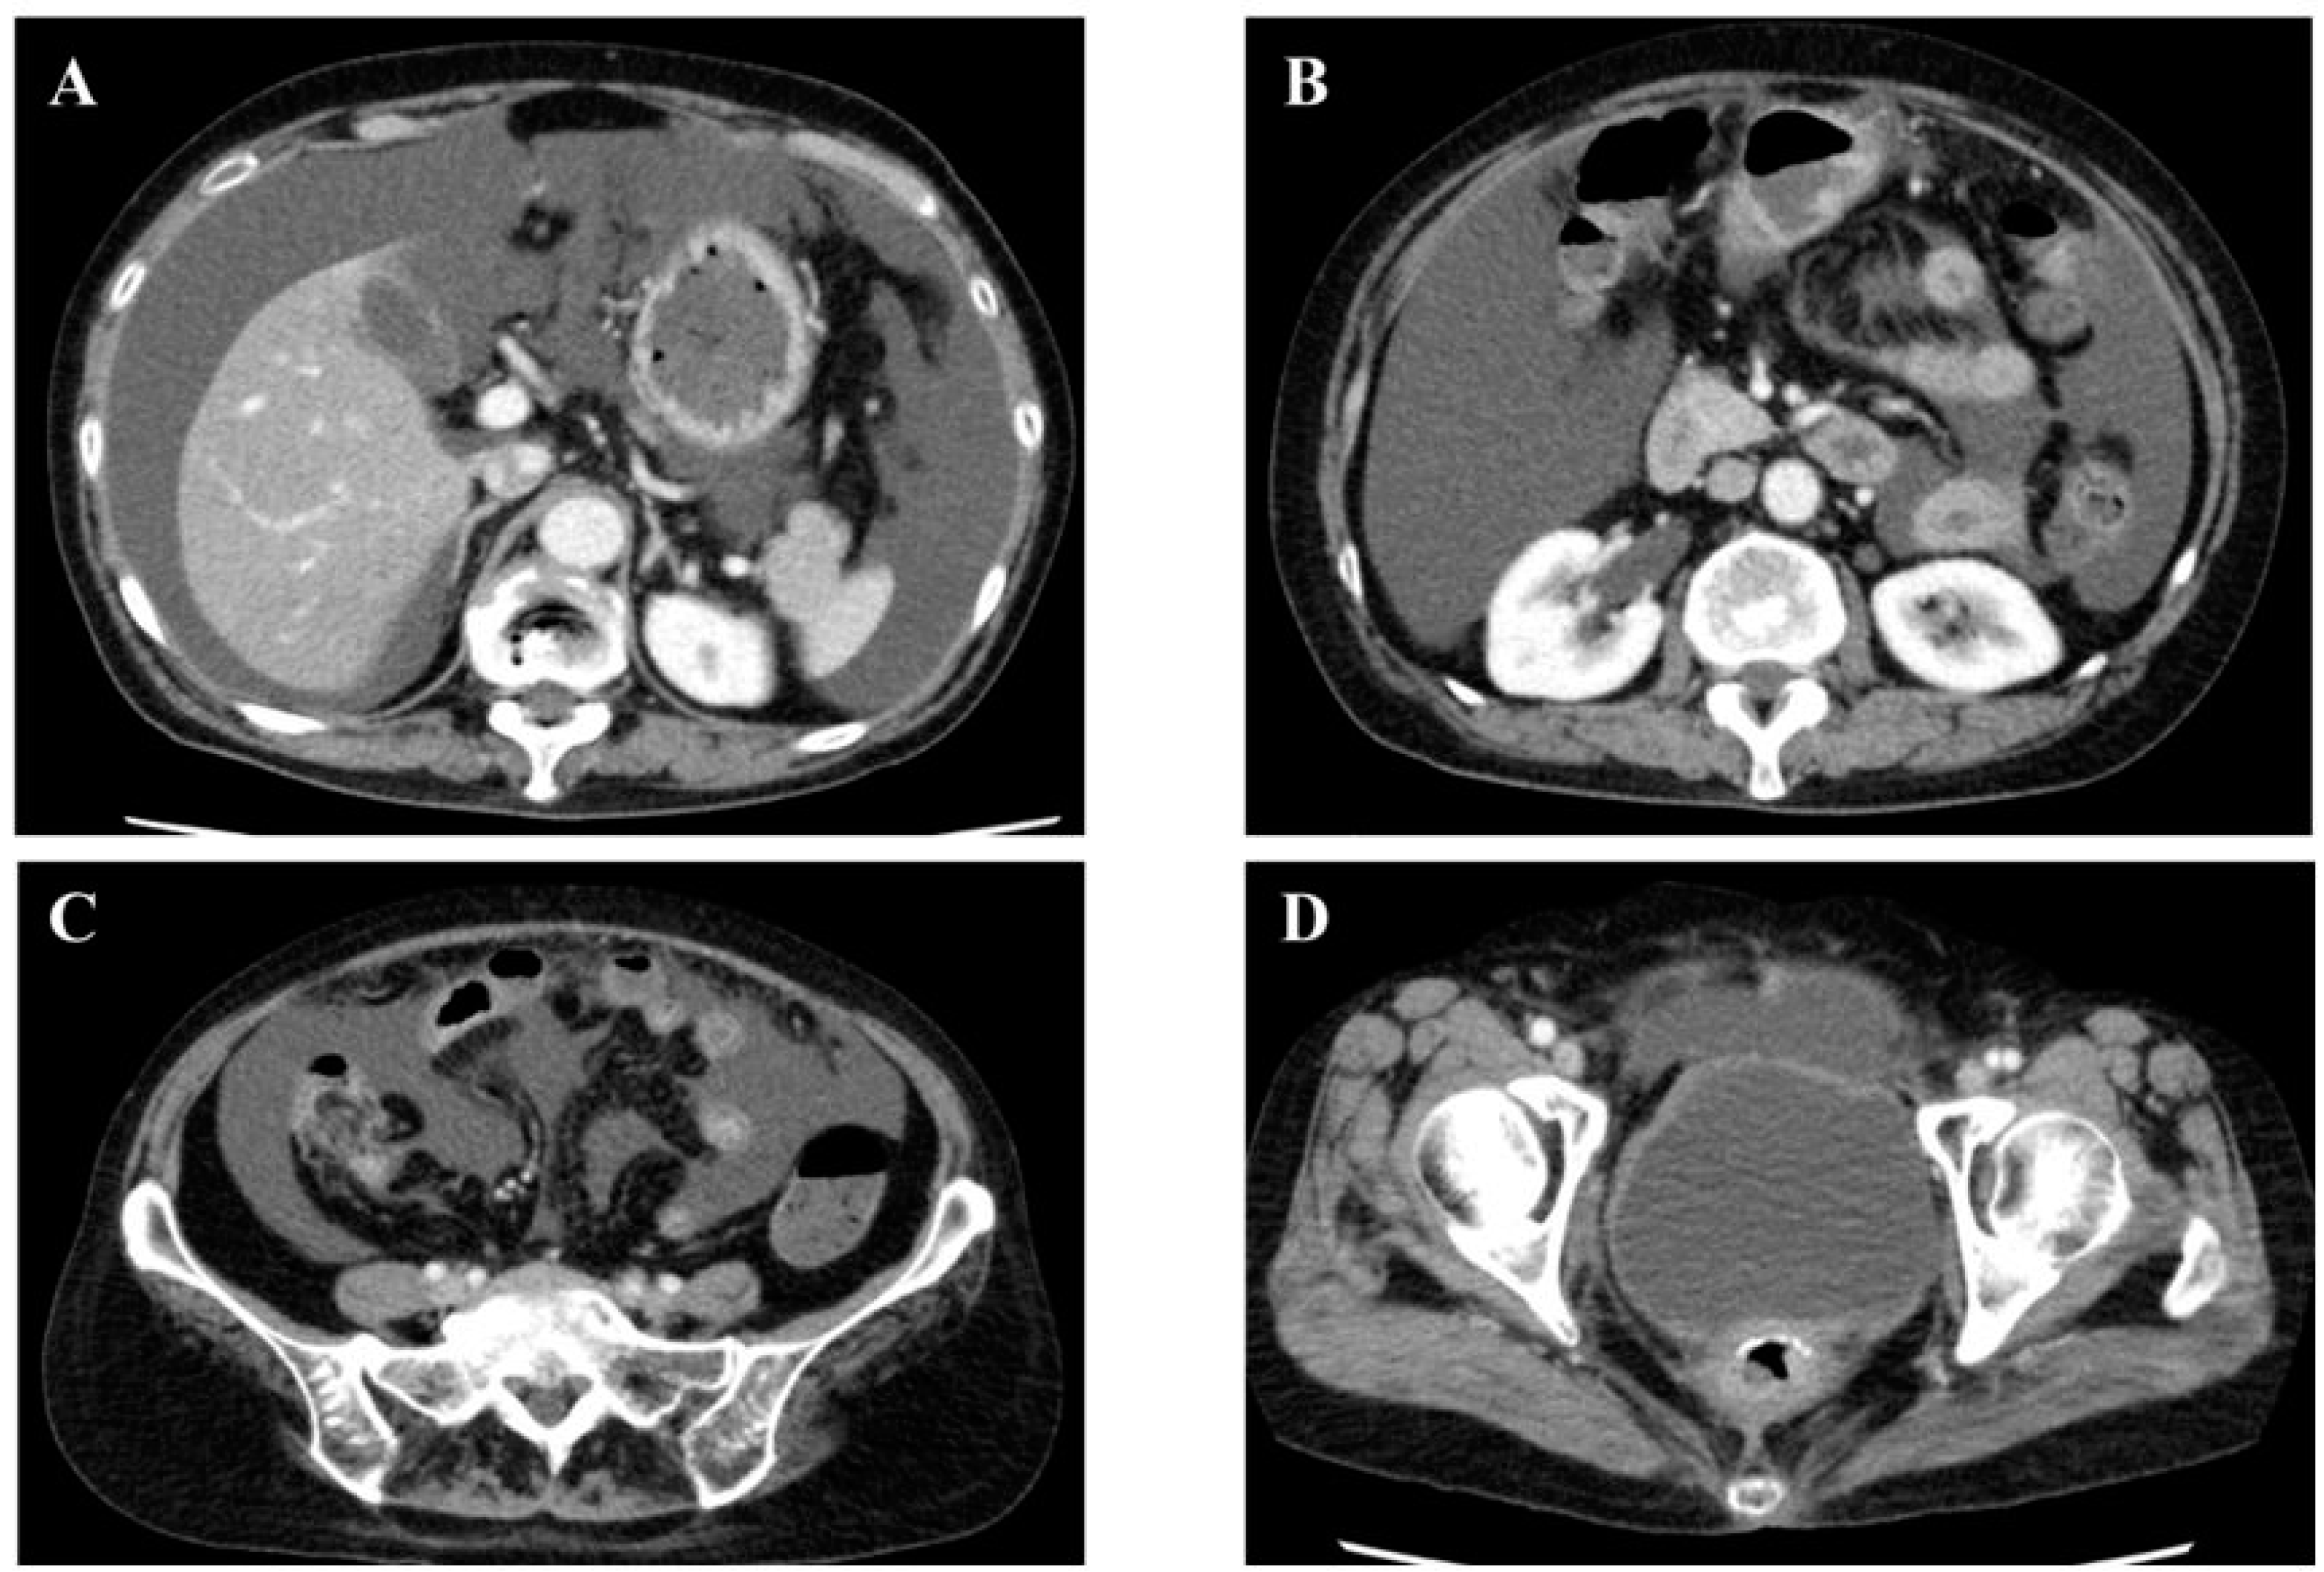

2. Case Report